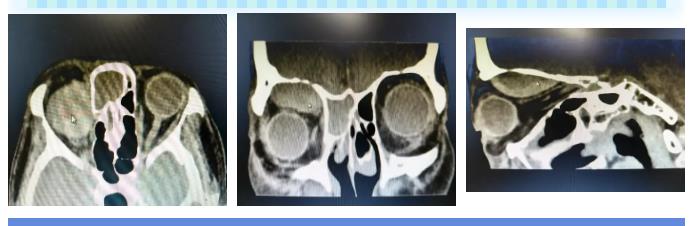

结合急诊眼眶CT检查,刘奶奶右侧眼球突出,眼眶上部存在混杂密度影,性质难辨(血肿/占位?),同时合并全副鼻窦炎,复杂病情直指右眼眶内肿物压迫——这不仅解释了眼球固定的根源,更预示着若不及时干预,视力将面临不可逆的毁灭性打击。